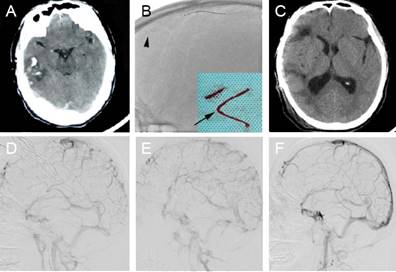

SH-CVST can cause massive hematoma, edema, and cerebral hernia, which can be fatal. Studies have shown that intracranial hemorrhage before treatment can lead to poor functional prognosis, higher incidence of permanent injury, increased risk of intracranial hemorrhage and higher mortality[10]. Under the circumstances, anticoagulation or thrombolytic therapy alone may further aggravate the hematoma. A retrospective study including eight patients who underwent stent retriever thrombectomy combined with long-term local thrombolysis (SRT-LLT) after unsuccessful intravenous anticoagulation between 2013 and 2018 achieved angiography-confirmed successful recanalization in all patients, with no treatment-related complications or deaths. Figure 3 shows an image of a patient who achieved hematoma absorption and edema dissipation after venous sinus thrombectomy (Fig. 3) [76]. This study showed that SRT-LLT is a feasible, safe and effective treatment regimen for SH-CVST, and can be used as a rescue treatment for specific SH-CVST patients[76]. A retrospective study was conducted to analyze the clinical data of 56 patients with SH-CVST admitted for 9 years, and all patients received LIST with or without MT. The complete recanalization rate was 67.8% and the good prognosis rate at discharge was 87.5%. The mRS score was 0-2 in 49 of the 51 patients who were followed up at 6 months after surgery. These results suggest that endovascular treatment may improve the clinical outcomes of most patients with SH-CVST, however, this needs to be confirmed in prospective controlled studies[77].

(A) A 47-year-old male patient presented with a headache and worsened in the next day. The computed tomography (CT) scan revealed right temporal lobe hemorrhage. (B) Stent retriever thrombectomy was performed. The arrow indicates the Solitaire FR stent deployed in the occluded superior sagittal sinus (SSS). The arrowhead indicates the clots that were removed. (C) The 4-month follow-up CT scan was normal, apart from the cranioplasty. (D) The lateral digital subtraction angiography (DSA) sinus phase image of the right side demonstrated extensive severe cerebral venous sinus thrombosis. (E) DSA revealed partial recanalization of the occluded sinus. (F) DSA revealed complete recanalization of the SSS with normal arteriovenous blood flow in the left transverse sinus at the 4-month follow-up. Reproduced with permission from Spandidos publisher (journal citation[76]). Copyright: © Wang et al.